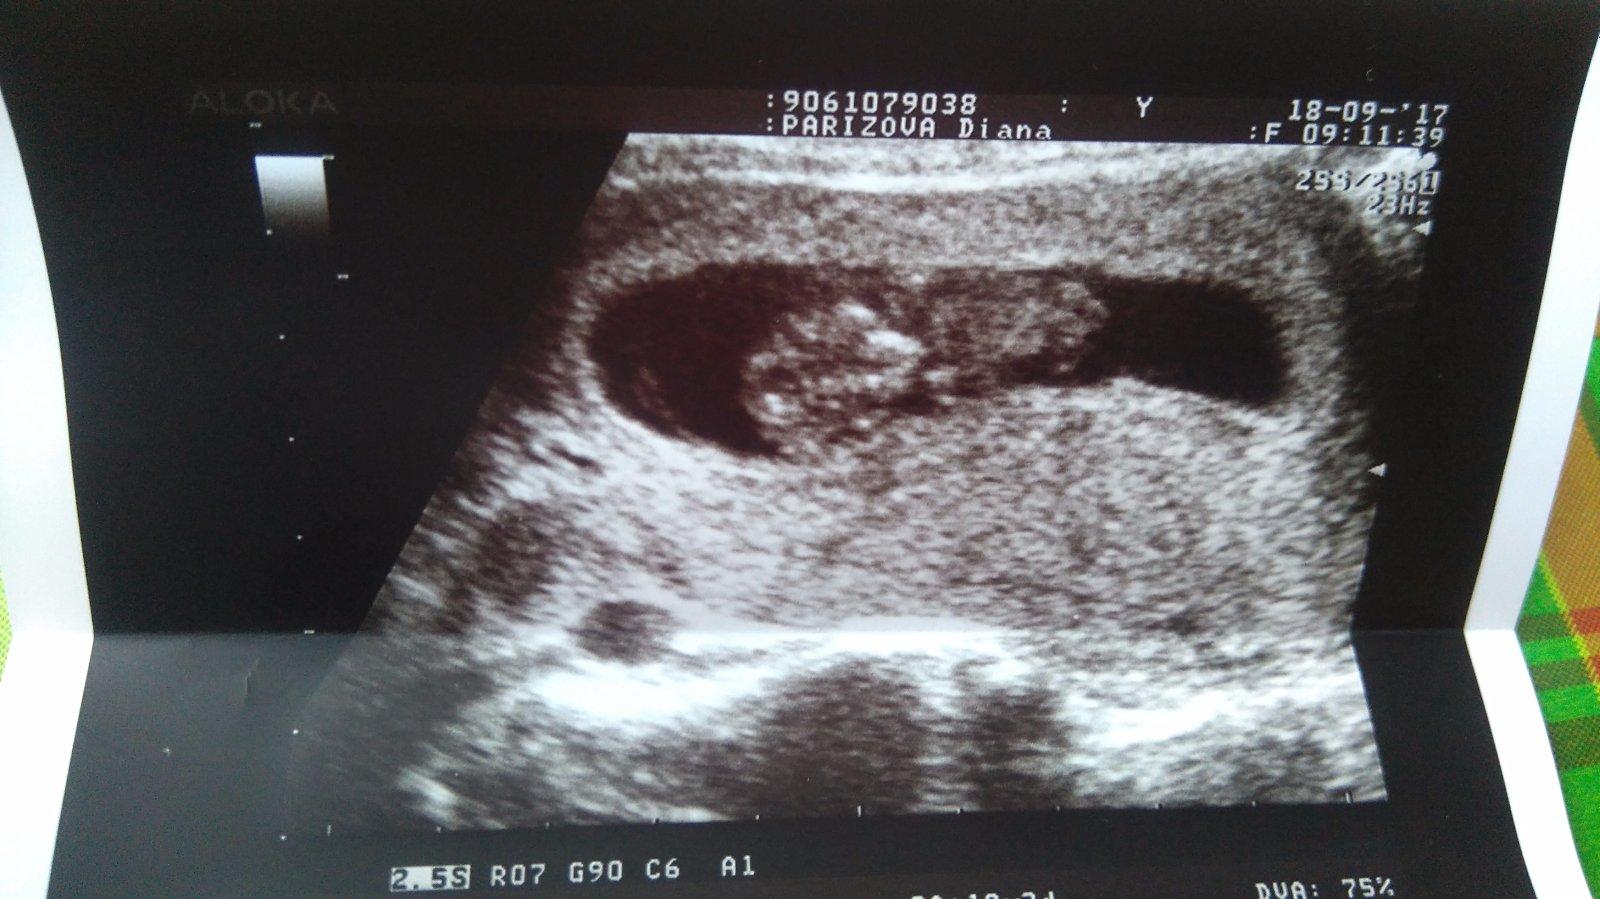

Babyyyyyy s radosťou "hlasim" 1DC 😁😁